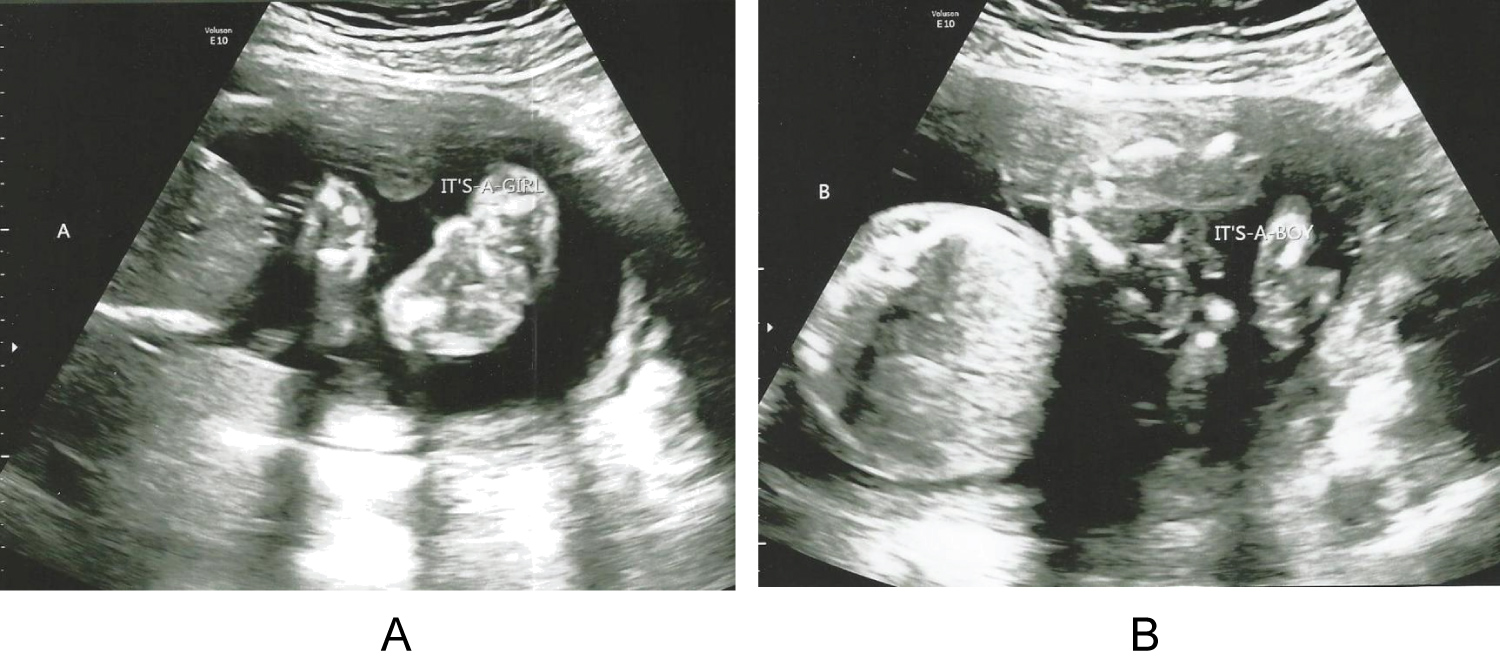

2 weeks later, the patient sought a second opinion at another tertiary care facility. Ultrasound again demonstrated a twin pregnancy (Figure 2A and Figure 2B).

Figure 2: (A) Ultrasound photo showing Twin A, Female, measuring 21 weeks; (B) Ultrasound photo showing Twin B, Male, measuring 19 weeks. View Figure 2

Measurements showed Twin A at 21 weeks and Twin B at 19 weeks. The twins were both morphologically normal and had normal amniotic fluid measurements. These findings argued against fetal triploidy. Also, at this time, the initial cfDNA test was recalculated, accounting for the twin gestation, and another new cfDNA sample was drawn. The recalculated initial cfDNA result came back insufficient fetal DNA for diagnosis. The new cfDNA sample drawn at 21 weeks and 2 days result came back low-risk. The patient decided to continue with the pregnancy with close follow up. Serial ultrasounds were performed that showed normal interval growth of both twins with the same discordance as the first ultrasound at 19 weeks and 2 days (Graph 1 and Graph 2).

As shown above in Figure 1A and Figure 1B, it is seen that in the 7-week ultrasound only one fetus is seen in the uterine cavity. Normally when a woman is pregnant with twins you will see 2 fetuses present in the uterus at the 7-week ultrasound. It is extremely rare to miss twins at a 7-week ultrasound, especially when they are diamniotic dichorionic. In Figure 2A and Figure 2B, it is seen at the 21-week ultrasound that 2 fetuses are shown in the uterine cavity for the first time. At this ultrasound growth discordance similar to the 19-week ultrasound was noted between Twin A and Twin B. Research has shown that initial cfDNA test fails (e.g., the results are not reported, indeterminate, uninterpretable, or no-call) have an increased risk of aneuploidy [8]. However, her first MFM consult did not discuss the possibility of a missed twin pregnancy diagnosis for this patient's initial high-risk cfDNA test. A missed superfetation twin pregnancy does explain her initial high-risk cfDNA result and the subsequent recalculated cfDNA being result of insufficient fetal DNA. The redrawn cfDNA test result of low-risk also points to two normal fetuses. On all of the subsequent ultrasounds that were done after 19 weeks there was always a consistent growth difference between the two fetuses but normal interval growth still occurred which is shown in Graph 1. Since there was normal interval growth on subsequent ultrasounds it goes against the idea of fetal growth restriction due to triploidy and points more towards superfetation as the cause for growth differences [5]. The placenta examination post-operatively also points toward superfetation. The second placenta was much smaller and appeared to be "smashed" up against the other more normal appearing placenta. The NICU course of stay and subsequent management of Twin B as being more premature than Twin A also points toward superfetation and not fetal growth restriction.